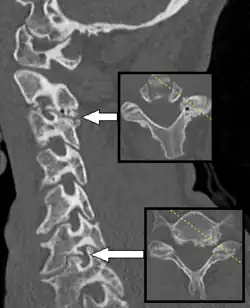

Axial skeleton and extremities

For the axial skeleton and extremities, CT is often used to image complex fractures, especially ones around joints, because of its ability to reconstruct the area of interest in multiple planes. Fractures, ligamentous injuries, and dislocations can easily be recognized with a 0.2 mm resolution.[71][72] With modern dual-energy CT scanners, new areas of use have been established, such as aiding in the diagnosis of gout.[73]

Multiplanar reconstruction and projections

Multiplanar reconstruction (MPR) is the process of converting data from one anatomical plane (usually transverse) to other planes. It can be used for thin slices as well as projections. Multiplanar reconstruction is possible as present CT scanners provide almost isotropic resolution.[109]

MPR is used almost in every scan. The spine is frequently examined with it.[110] An image of the spine in axial plane can only show one vertebral bone at a time and cannot show its relation with other vertebral bones. By reformatting the data in other planes, visualization of the relative position can be achieved in sagittal and coronal plane.[111]

New software allows the reconstruction of data in non-orthogonal (oblique) planes, which help in the visualization of organs which are not in orthogonal planes.[112][113] It is better suited for visualization of the anatomical structure of the bronchi as they do not lie orthogonal to the direction of the scan.[114]